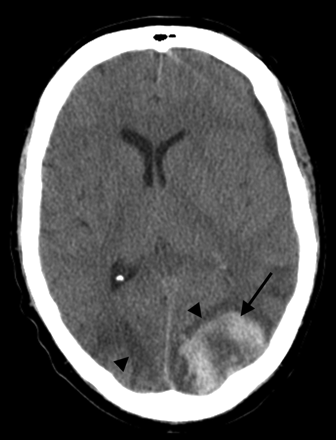

A 50-year-old man status post allo-BMT for acute myelogenous leukemia. CT scan demonstrates PRES vasogenic edema in the parietal region bilaterally (arrowheads), along with an acute hematoma in the left parietal lobe (arrow).